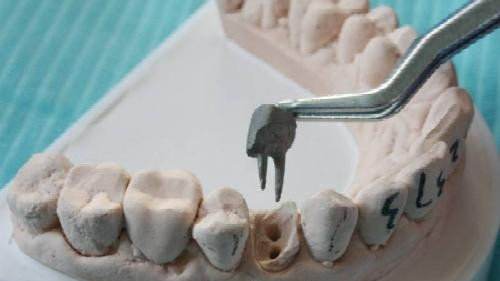

3、確定根管工作長(zhǎng)度:應(yīng)用平行投照X線(xiàn)方法、根管長(zhǎng)度測(cè)量?jī)x確定根管度,好插針拍X片。

4、根管預(yù)備:根管清理成形的目的是去凈根管壁上的感染物,通過(guò)根管器械的切削作用去除感染的牙本質(zhì)并清理根管壁細(xì)菌以利于根管充填。

7、根管打樁:因牙體缺損過(guò)多,導(dǎo)致牙的強(qiáng)度(承受力量的性能)大幅度下降,不能很好地承受咀嚼力量。打樁的目的是增加牙根及牙冠的強(qiáng)度,增加患牙的穩(wěn)固。